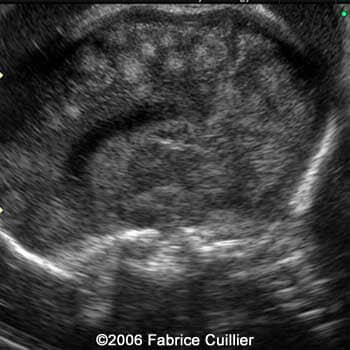

An additional endovaginal scan was performed. There were one large cyst on the right hemisphere and multiple peripheral cysts. The corpus callosum artery was identified. Fetal biometry was in concordance with the gestational age. Karyotyping was offered (46XX). A PCR was performed in the amniotic fluid sample. The result was positive for the Toxoplasma gondii DNA.

Brain sagittal scan at 30 weeks showing the corpus callosum artery

8

9